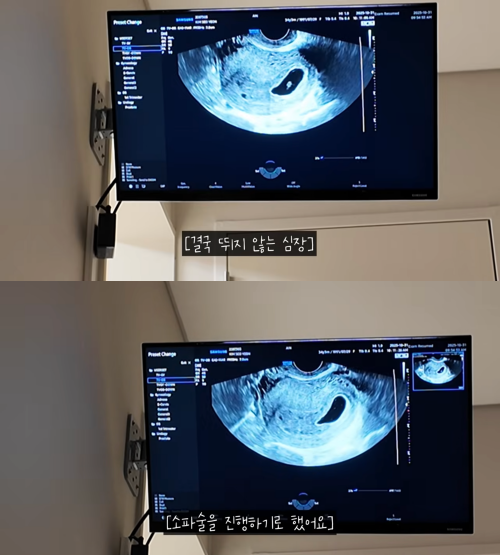

초음파 검사를 진행하던 의사는 “아주 미세한 움직임이 있지만 정상적으로 임신이 진행될 가능성은 1~2% 정도로 매우 낮다”며 “심장이 뛰기 시작했지만 속도로 보면 60회 안쪽이다. 희망을 가지기 어려운 상황”이라고 조심스레 설명했다. 로빈, 김서연 부부는 “안 좋은 확률이 많지만, 하늘이가 조금 더 붙어있고 싶었나 보다”며 3일을 더 기다려 보기로 했다.

그러나 다시 찾은 병원에서 아기의 심장은 더 이상 뛰지 않았다. 의사는 “아기가 만들어지는 과정은 신의 영역이다. 이런 일은 전체 임신 중 7~10%에서 발생한다”며 “이번에는 아기 쪽 문제로, 다음 임신에는 영향이 없을 것”이라고 위로를 건넸다.